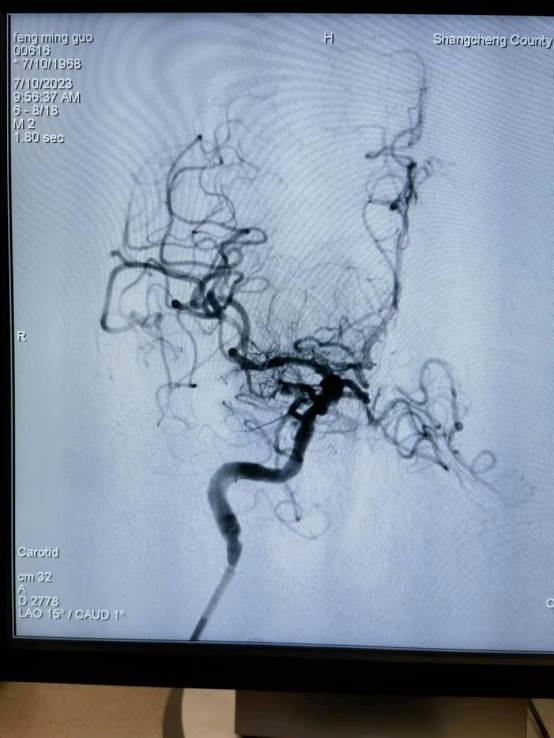

近日,55岁的冯先生突发急性脑梗死,我院卒中中心启动绿色通道,给予静脉溶栓桥接取栓治疗,成功打通堵塞的“生命管道”,患者转危为安,术后恢复良好,避免了“一人中风,全家瘫痪”的悲剧。

冯先生的成功救治,是静脉溶栓桥接动脉取栓治疗的完美结合。这次抢救工作的完美收官依靠的绝不仅仅是个人能力,它是整个团队共同努力的结果,检验了我院卒中中心对于脑卒中患者的快速鉴别诊断及多学科协作救治能力。我院卒中中心就是这样一支这样技术精湛、素质过硬的团队,在卒中介入治疗领域已经具备较强的综合实力,他们始终秉持着时间就是大脑、时间就是生命的理念,不断优化卒中急救模式和流程,为保障大别山区卒中患者能够得到及时、规范、有效的救治,降低县域卒中死亡率、致残率而不懈努力,为助力全面建设健康中国贡献自己的力量。